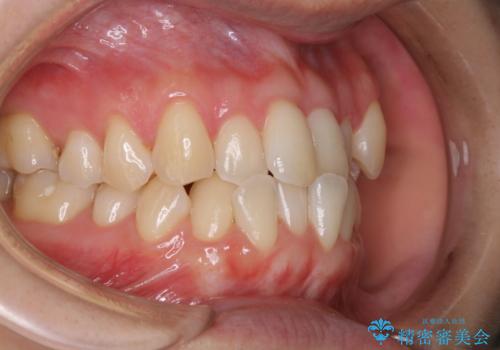

- 矯正治療がまもなくスタートするため、きれいにしたいのと歯磨きを上達したいとのことでした。染め出しをしての歯磨きチェック・指導とPMTC30分コースを行いました。